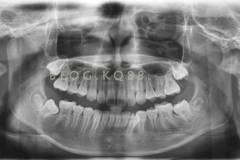

下面這個(gè)小患者就存在需早期矯正的問題。通過早期矯正,在不長(zhǎng)的時(shí)間內(nèi)就達(dá)到極為明顯的療效。她的情況如果等到牙齒替換完畢后再解決,矯治的難度則會(huì)非常大。

部分早期矯正裝置